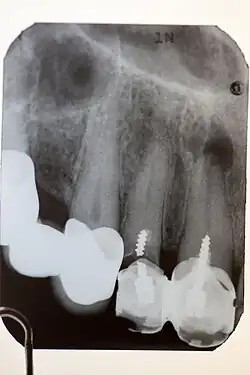

Stiftaufbau an Zahn 11 und 12, der nicht dem heutigen Standard entspricht: zu kurz, geschraubt, gebrochen an Zahn 12, ohne Wurzelfüllung, Wurzelgranulom an Zahn 11